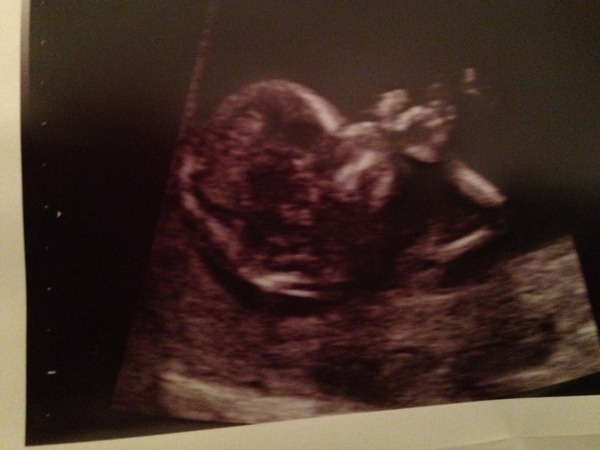

Hi everyone had scan today , I'm officially 12 weeks and 2 days baby due on the 14 th of September. Nt scan put at 1.5 hopefully that's good ... Full results in two weeks. No HB for me as the worried about bleeding afterwards and no going over 40 weeks.

Congratulations lola! The best milestone to pass! Is it me, or is your baby clutching its head and sucking its fingers? Very relaxed!

Thanks stubborn glad 28 week check went well ... It's horrible when you can't sleep , I'm sure it's getting you ready for those sleepless nights to come. Baby had hands on it's face ... It's all a bit real now Smile

Looks like baby is blowing you a kiss, Lola!

Fabulous scan pic Lola. The 12 week one always feels like such a massive milestone to pass. Yay! Glad your 28 week check went well stubborn

Oh yes, NT of 1.5 sounds good and normal too, lola x

So lovely to see the scan picture, Lola. The baby's hand position is really sweet, like s/he is snuggling up ready to sleep. It must be great to have that milestone complete successfully. Mine is two weeks tomorrow and I'm both counting the days as I can't wait and dreading it at the same time. I feel like the baby has to pass an exam!

Thanks cineraria, know exactly how you feel about baby having to pass an exam, it's a frightening and exciting all at the same time. Just got to wait for the combined results to come back roughly two weeks and then I will feel happy to share the news with family.